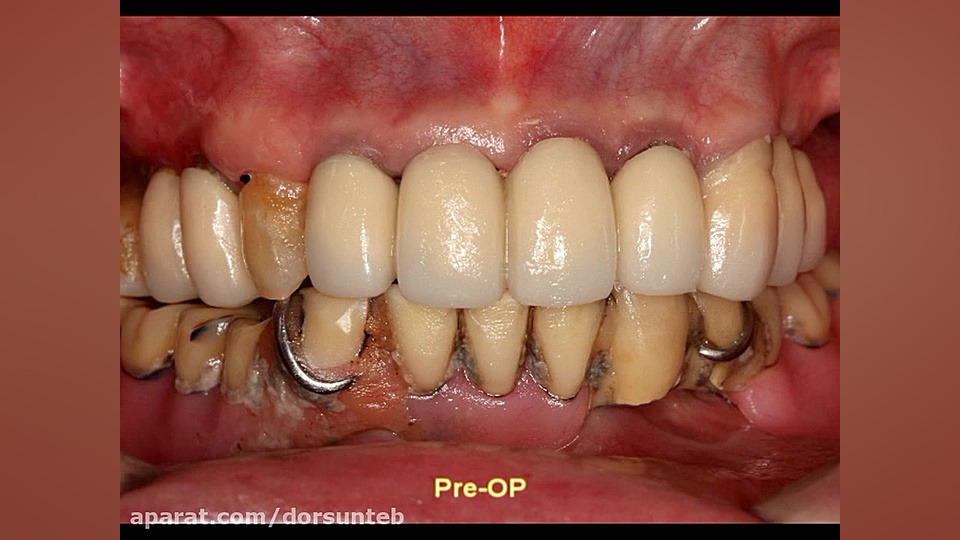

Immediate implantation using Implant Guide2